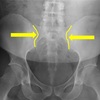

AP LUMBOPELVIC LANDMARKS A-P lumbopelvic view

femur heads

110

A-P lumbopelvic view

superior iliac crests

111

lateral iliac crests

112

ischial tuberosities

113

s2 tubercle

114

pubic/pubic symphysis

115

sacral grooves

116

lateral aspect of sacrum

117

medial aspect of ilium

118

obturator foramen

119

spinous processes

120

supeiror endplate tips

121

lumbar pedicle shadow